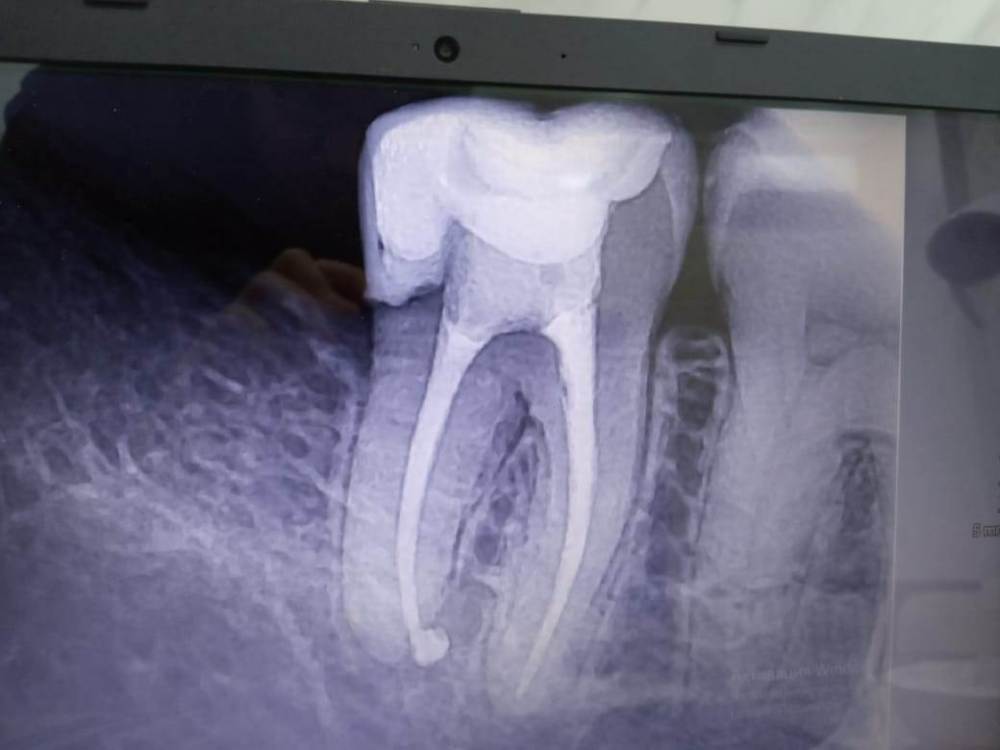

Aleksandr21321 Опубликовано 16 января, 2024 Поделиться Опубликовано 16 января, 2024 Вот снимки, но врач сказал, что снимкам не стоит на 100% доверять. Болит зуб или даже зубы при употреблении пищи, а также присутствует временами постоянное нытье зуба / зубов. Что делать, я и врачи (ходил к нескольким) совершенно не понимаем. Дело в том, что определить кто именно виновник, трудновато. В одном из зубов удален нерв, и при надавливании чувствуется, что ему некомфортно. Но не факт, что виновник проблем именно он... В интернете упомянул кто-то компьютерную томографию, которая стоит недешево. Скажите, стоит ли ее делать и как она поможет? Ссылка на комментарий

АнтонТЛТ Опубликовано 16 января, 2024 Поделиться Опубликовано 16 января, 2024 В нижнем 7 зубе щель между пломбой и зубом в районе корня под десной. Ссылка на комментарий

Aleksandr21321 Опубликовано 16 января, 2024 Автор Поделиться Опубликовано 16 января, 2024 (изменено) 47 минут назад, АнтонТЛТ сказал: В нижнем 7 зубе щель между пломбой и зубом в районе корня под десной. Из за этой щели может болеть при жевании? КТ стоит делать, чтобы подтвердить щель, а также узнать, может где нерв близок к пломбе? Или последнее и снимки показывают? Изменено 16 января, 2024 пользователем Aleksandr21321 Ссылка на комментарий

АнтонТЛТ Опубликовано 16 января, 2024 Поделиться Опубликовано 16 января, 2024 Может. На КТ будет хуже видно Ссылка на комментарий

Aleksandr21321 Опубликовано 16 января, 2024 Автор Поделиться Опубликовано 16 января, 2024 1 час назад, АнтонТЛТ сказал: Может. На КТ будет хуже видно а мне мой врач наоборот сказал, что конкретно близость нерва к пломбе КТ лучше показывает, чем обычные снимки. странно.. Ссылка на комментарий

АнтонТЛТ Опубликовано 16 января, 2024 Поделиться Опубликовано 16 января, 2024 Пломбы могут фонить на кт Ссылка на комментарий